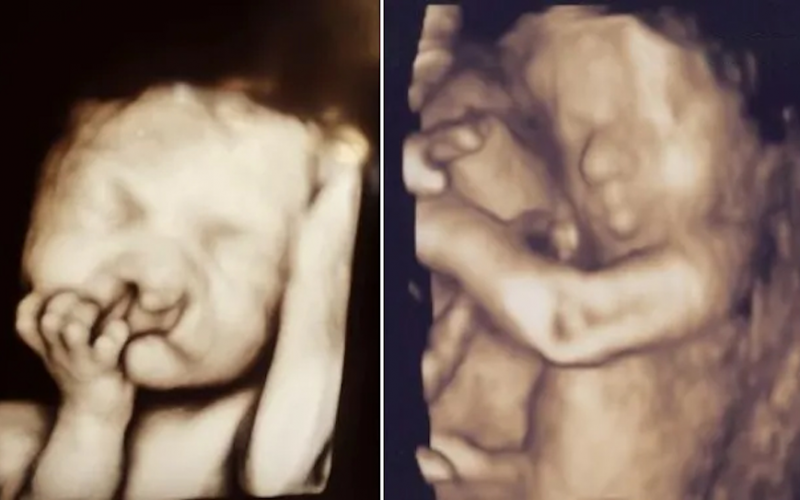

When she was just 24-weeks pregnant, Sarah learned that her unborn baby had a cleft lip and palate. Her partner, Chris, was shocked to hear the news. They reportedly got a lot of criticism from people, including those who were supposed to be in charge of care. Nevertheless, both parents wanted to share as many pictures as they could with their baby, despite his deformity. Later, Sarah realized just how supportive people were of their child.